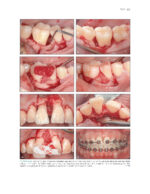

The Ortho-Perio Patient: Clinical Evidence and Therapeutic Guidelines 2019

کتاب افست ” The Ortho-Perio Patient: Clinical Evidence and Therapeutic Guidelines 2019 ” ویرایش اول